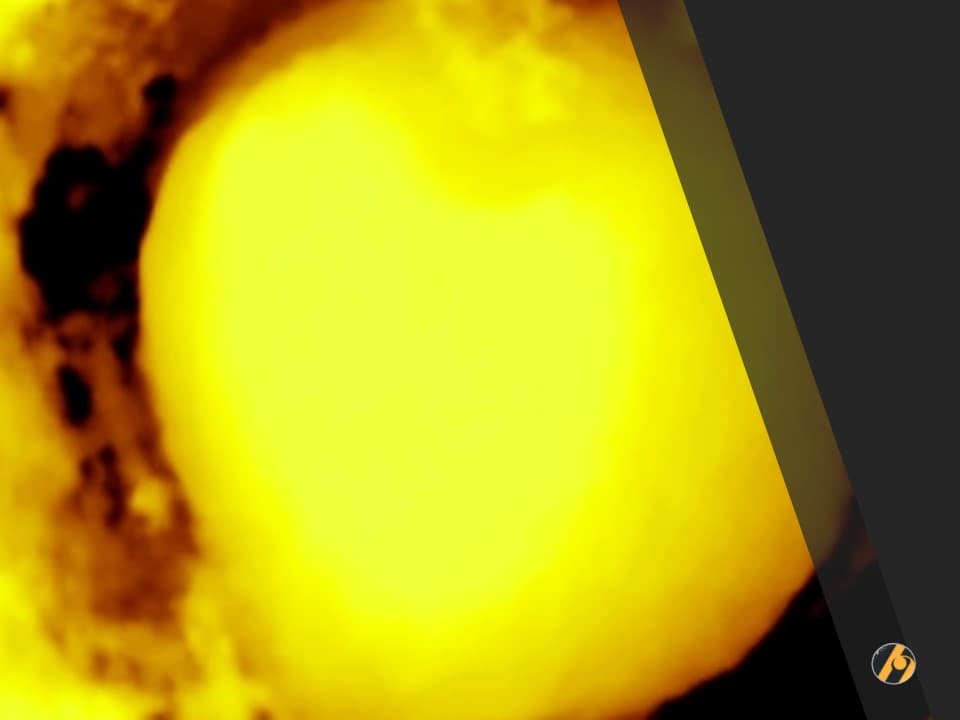

Color score

IOTA color score se temelji na subjektivnoj procjeni protoka krvnih žila color dopplerom unutar tumorskog tkiva.

- Color score 1 znači da nema detektabilnog dopplerskog protoka.

- Color score 2 znači minimalnu prisutnost doppler signala.

- Color score 3 znači umjerenu prisutnost dopplerskih signala.

- Color score 4 znači obilnu prisutnost dopplerskih signala.

Kada se procjenjuje color score, moraju se prilagoditi setinzi i prikazati maksimalan protok bez artefakata (Pulse Repetition Frequency PRF 0,3 – 0,6 KHz, zatim pojačavati gain dok se ne pokažu artefakti, tada lagano smanjiti da se ne vide).